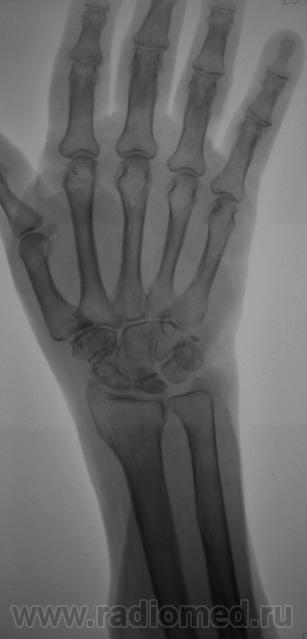

Пол пациента: Женский пол Тип патологии: Травма Область исследования: Скелетно-мышечная система Методы исследования: Rg Травма. Пациентка направлена на рентгенографию лучезапястного сустава. https://radiomed.ru/sites/default/files/styles/case_slider_image/public/user/12/2.pc240002.jpg?itok=EmMPdPhA https://radiomed.ru/sites/default/files/styles/case_slider_image/public/user/12/3.pc240003_0.jpg?itok=3uQRKsB7 https://radiomed.ru/sites/default/files/styles/case_slider_image/public/user/12/4.pc240004_0.jpg?itok=4sdd2ZGB ID:10581 Вс, 26/12/2010 - 17:09 #1 Сан Саныч1 Не на сайте Был на сайте: 11 месяцев 1 неделя назад Зарегистрирован: 07.06.2010 - 21:17 Публикации: 2114 Валентин Львович, здравствуйте. А можно боковой покрупнее? Хочешь сделать что-то нормально - сделай это сам! Вс, 26/12/2010 - 21:10 #2 ortoped1984 Не на сайте Был на сайте: 11 лет 10 месяцев назад Зарегистрирован: 02.11.2010 - 19:28 Публикации: 29 Не болезнь ли Кинбека?

Не болезнь ли Кинбека?